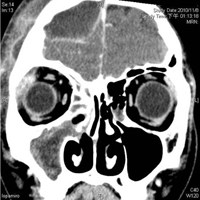

一名14歲男童,連續一星期多出現咳嗽、流鼻涕現象,因持續發燒、頭痛三天,就醫後發現是右側眼窩、硬腦膜上膿瘍及鼻竇感染,住院期間經過手術及適當藥物治療後,情況已經好轉,出院後持續口服抗生素,終於解決頭痛及發燒問題,後續使用抗過敏藥物改善過敏性鼻炎。

他說,兒童鼻竇炎常發生在過敏體質的兒童身上,常見症狀包括鼻塞、持續咳嗽、流黃膿鼻涕、鼻涕倒流、頭痛等症狀,臨床上常被誤以為是感冒,所以根據病史及臨床檢查及早發現是重要課題。